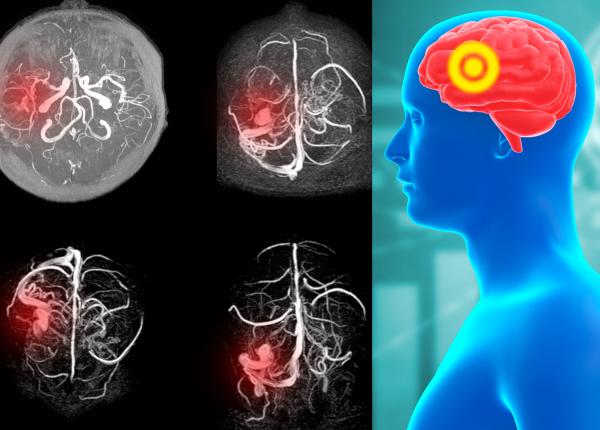

EXCLUSIV Anevrismul, cauza morții subite: E ca o foiță de ceapă, plesnește în cap! Putem să-l avem și noi, oricând. Tineri de 14 - 18 ani cad din picioare și mor

Anevrismul, cauză a sindromului morții subite. Tehnica medicală a scăzut riscul de deces din cauza anevrismului.

EXCLUSIV Anevrismul, o URGENȚĂ medicală neglijată. Cum știi dacă-l ai. Atenție dacă te-ai CERTAT, ai zburat cu avionul sau te doare capul. Ciurea: POC, a pocnit un vas în cap